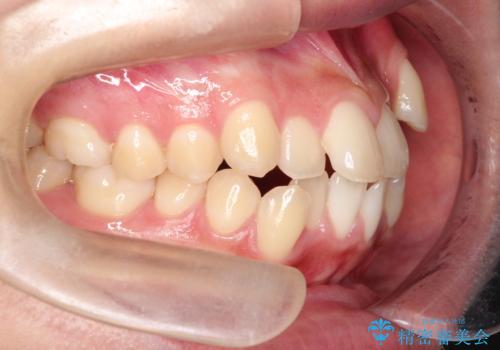

- 八重歯と口元が出ていることを主訴に来院されました。

レントゲンの検査において、前歯も外側に傾いてる結果であったため、上下左右の小臼歯を抜歯して配列を行いました。